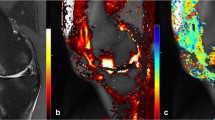

Image analysis

To correct for patient movement, all 35 time points of the DCE-MRI were registered using an automated rigid body registration with Elastix [26]. We first assessed the fat-saturated T2-weighted images for the presence of T2FS-hyperintense regions in the IPFP. Subsequently, detected T2FS-hyperintense regions were delineated on the quantitative T2 maps. The delineation of ROIs was performed on T2 maps as these images were scanned in the same part of the scan session as the DCE-MRI, in contrast to the T2FS-weighted images, and thus the regions of interest (ROIs) could be copied to the DCE-maps. ROIs were placed within the borders of the hyperintense regions using the Horos software package (Horosproject.org). When multiple hyperintense regions were found in the IPFP, the ROI was placed in only one, the largest region. Two ROIs were drawn in the IPFP, one within the T2FS-hyperintense region and the second in an adjacent area without T2-hyperintensity (Fig. 1). All ROIs were drawn by a researcher with a technical medical degree and more than three years of experience in musculoskeletal imaging research (B.d.V.). The same ROIs from the T2-maps were copied to the registered DCE-MR images to extract quantitative DCE measures from the same regions. These quantitative DCE parameters (Ktrans, Kep, Ve, Vp) were calculated by fitting the extended Tofts pharmacokinetic model to the DCE-MRI data, using the DCETool in Horos [27, 28]. Subsequently, mean T2 value and mean perfusion parameter values of the ROIs were calculated. The Tofts pharmacokinetic model is widely used for this purpose and has shown to be the most accurate model for patellar bone [29]. For highly vascularized tissues, like the IPFP, the extended Tofts pharmacokinetic model is more suitable due to the addition of the vascular term Vp; therefore, in this study, we used the extended Tofts pharmacokinetic model [30]. Ktrans reflects the volume transfer constant into the tissue compartment, Kep describes the rate constant back into the vascular component, Ve is the extravascular extracellular space, and Vp is the vascular fraction of the region [31]. The arterial input function (AIF) was estimated using a ROI in the popliteal artery. All fitted AIFs were visually checked.